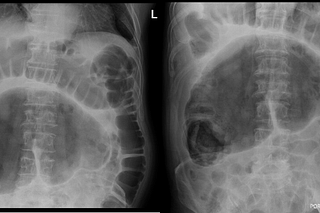

Cecal Volvulus

Jacob C Davis, DO

Apr 5, 2025

2